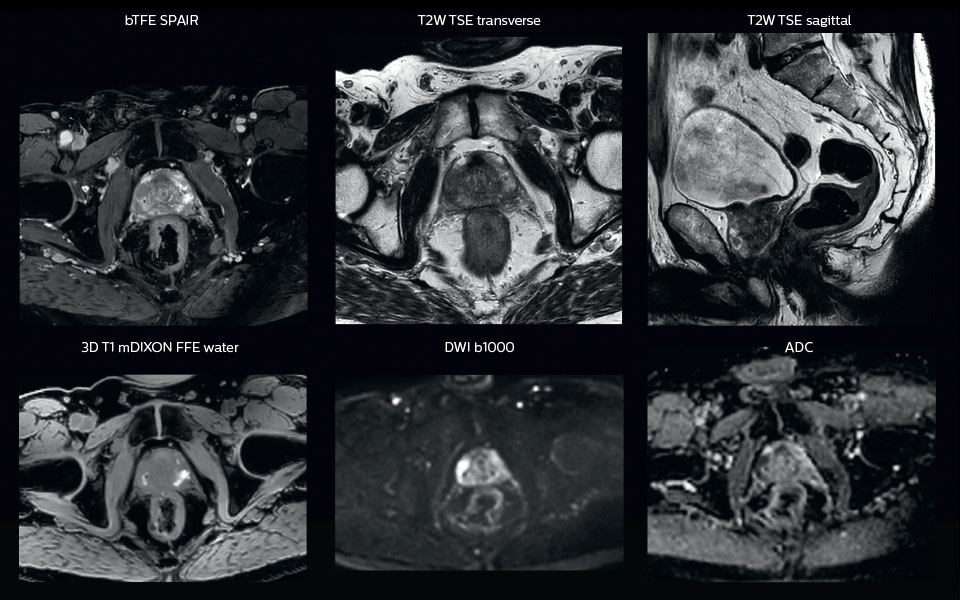

“All our patients undergo an MRI exam – along with CT – before radiotherapy of the prostate,” says Dr. Philippens. “For prostate delineation, we are scanning a balanced TFE with fat suppression. We can also see the gold fiducial markers in these images, which are used for position verification and are therefore used for registration to CT. For geometric accuracy of the image, we choose a 3D sequence, which is corrected for the gradient non-linearities in all directions.

“In addition to helping in delineation of the prostate, MRI also helps in visualizing the lesions inside the prostate, which may not be possible in CT.

“When we can visualize intraprostatic lesions, the radiation therapist can then plan to boost them, giving a higher dose to those lesions instead of giving a uniform dose to the whole prostate, in the hope to better treat the patient and have less risk of recurrent tumors. However, this is not yet clinical routine. For visualizing the lesions, we not only use anatomical, T2-weighted imaging, but also diffusion weighted MRI and dynamic contrast- enhanced MRI."

Visualizing critical structures with MRI before prostate radiation therapy

A 63-year-old patient with prostate cancer, cT3bNxM, Gleason 7, underwent MRI on Ingenia 3.0T MR-RT before radiation therapy.

Intraprostatic lesions are visible on the bTFE MR image, but not on the CT image. MRI shows excellent soft-tissue contrast for the visualization of critical structures like the rectum and penile bulb.

Fiducial markers (green arrows) are used in registration of MR images to CT, to transfer the MR-based delineations onto the CT image dataset.